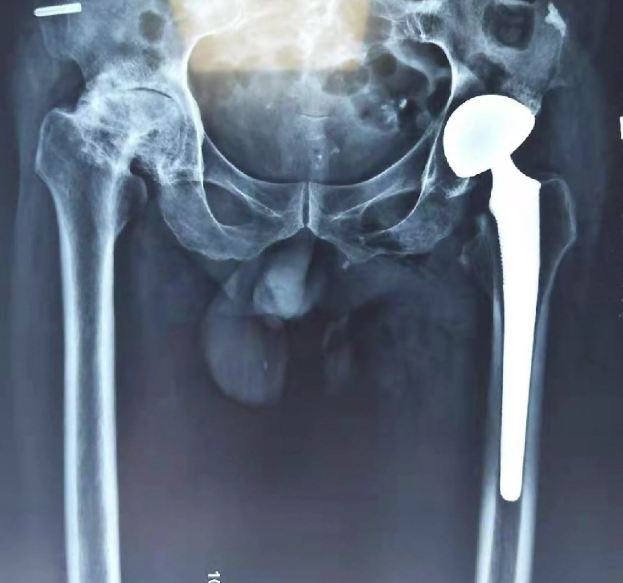

來到棗莊誠德骨科醫(yī)院救治后,得到了專家的精心治療。據(jù)劉德俊院長介紹,薛先生被診斷為雙側(cè)股骨頭壞死,雙側(cè)全髖關(guān)節(jié)骨性關(guān)節(jié)炎,骨質(zhì)增生非常嚴(yán)重,整個髖關(guān)節(jié)不能活動,走路呈剪刀腿形狀,治療比較復(fù)雜,有一定困難,為此,全院組織專家進(jìn)行了會診,拿出了一套系統(tǒng)、安全,科學(xué),先進(jìn)的治療方案。由于他的病情比較復(fù)雜,專家組分兩次進(jìn)行了手術(shù),手術(shù)很成功。

后期又在棗莊承德骨科醫(yī)院進(jìn)行了專業(yè)的康復(fù),幾個療程的康復(fù)讓他恢復(fù)了正常的走路